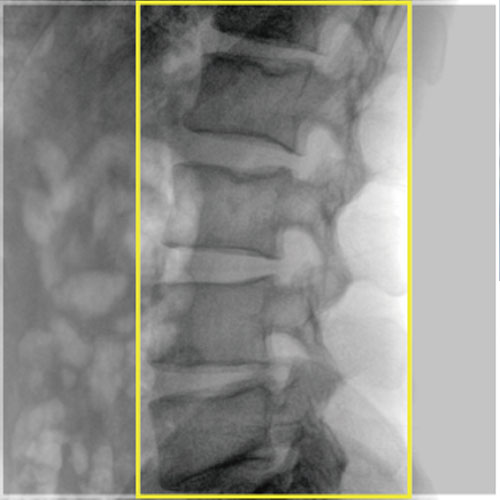

• Orthopedics

• Adjustable SID: The FPD can be lifted in a wide range to flexibly adjust SID and be close to the examination area for clearer fluoroscopic images.

• 12-inch dynamic FPD: Large dynamic FPD with smaller pixel size, ensuring distortionless imaging; Wider FOV, avoiding overlapping and omissions, reducing exposure time and radiation dose, and shortening the operation time.

Effectively satisfying the imaging requirements of obese patients or thick parts of high-density tissues;

Fully meeting the needs of high-power instantaneous exposure in digital radiography, especially suitable for peripheral intervention and comprehensive intervention.